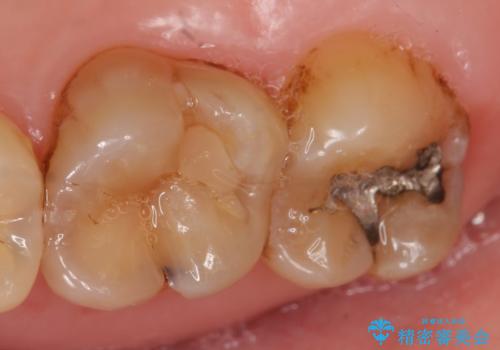

- 古い銀歯をセラミックで治療したいといらっしゃった方の症例です。

銀歯及び虫歯を除去後、セラミックインレーによる修復を行いました。